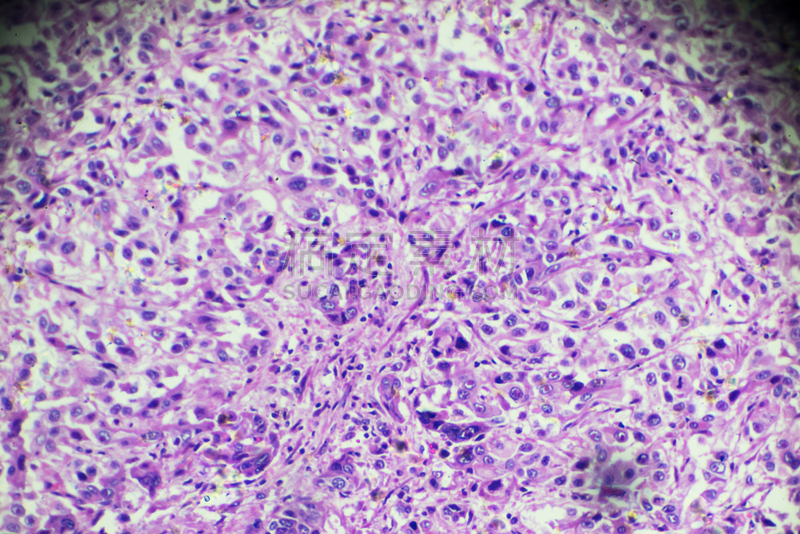

详情

JPG